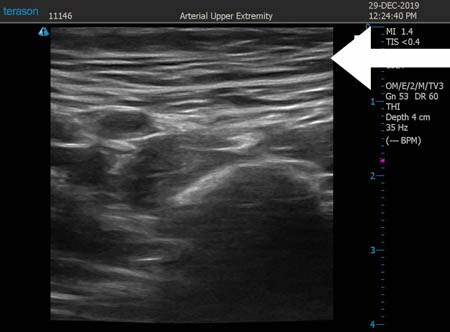

同様に右太もも前面。 ↓ ↓ ↓

↓ ↓ ↓